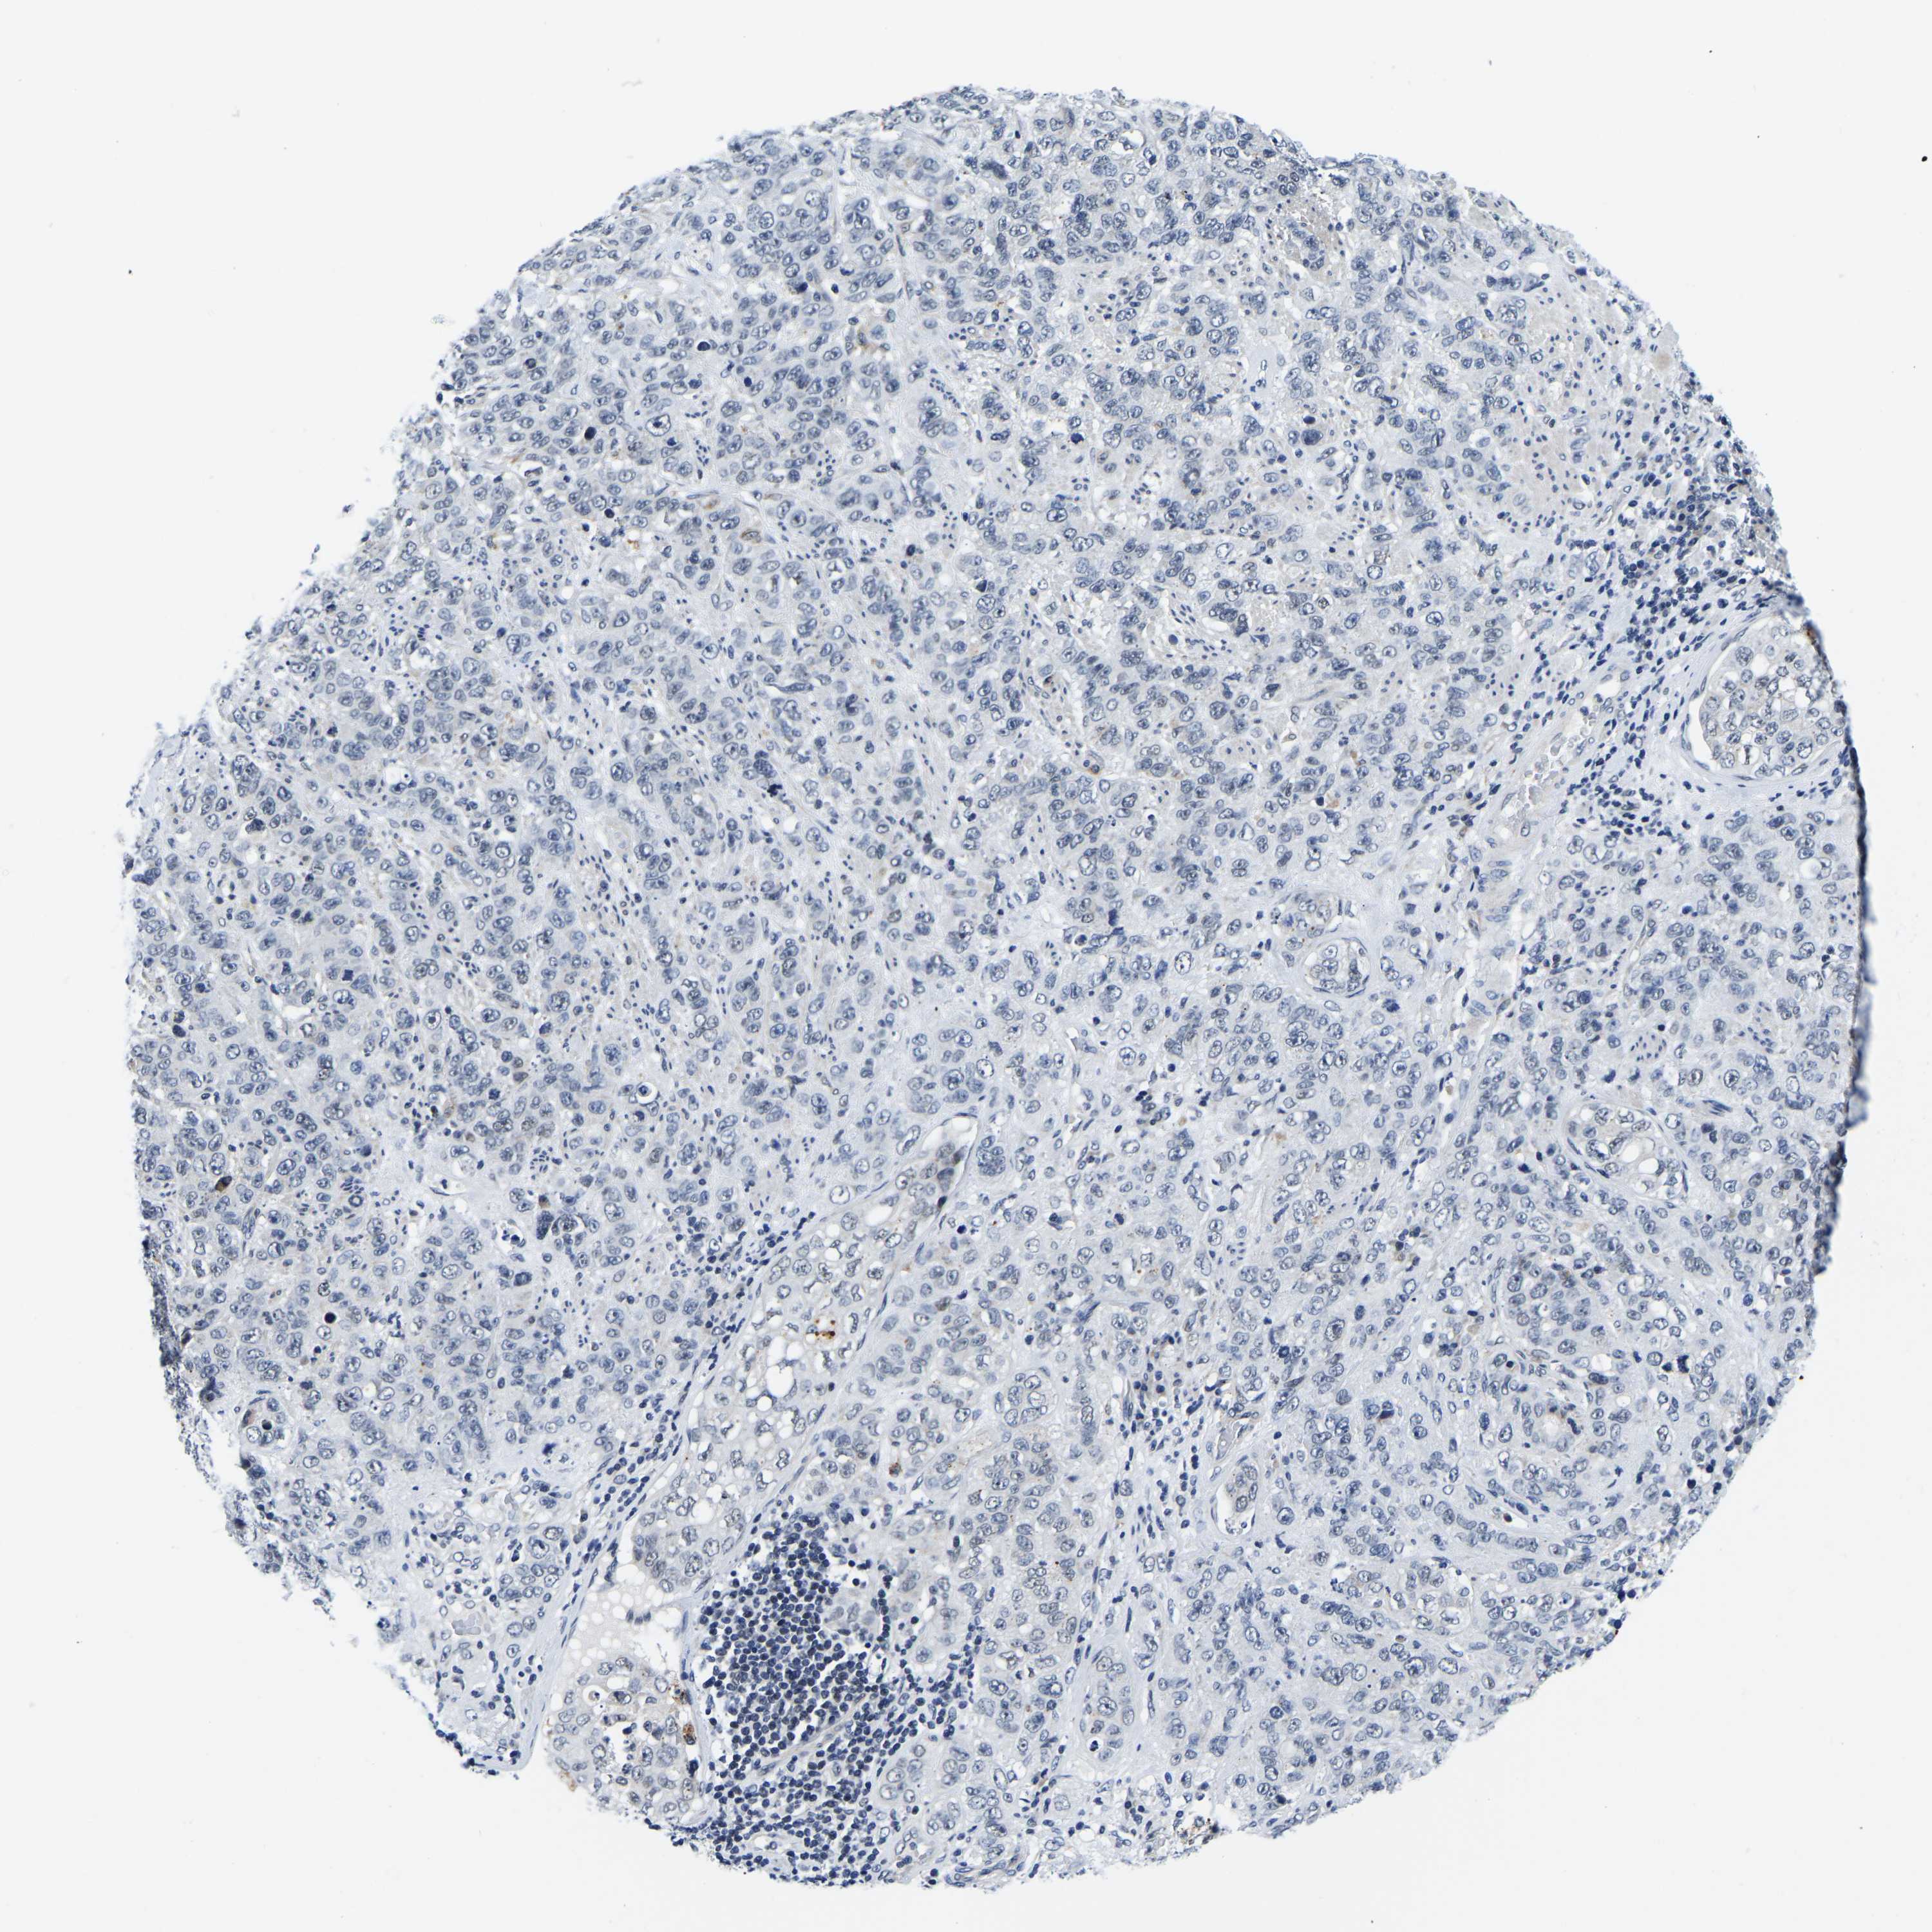

STOMACH CANCER - Protein expressioni

A mouse-over function shows sample information and annotation data. Click on an image to view it in a full screen mode. Samples can be filtered based on level of antibody staining by selecting one or several of the following categories: high, medium, low and not detected. The assay and annotation is described here.

Note that samples used for immunohistochemistry by the Human Protein Atlas do not correspond to samples in the TCGA dataset.

Antibody stainingi

Antibody staining in the annotated cell types in the current human tissue is reported as not detected, low, medium, or high, based on conventional immunohistochemistry profiling in selected tissues. This score is based on the combination of the staining intensity and fraction of stained cells.

Each image is clickable and will lead to virtual microscopy that enables deeper exploration of all samples and also displays staining intensity scores, fraction scores and subcellular localization as well as patient and tissue information for each sample.

Antibody HPA018419

Antibody HPA048790

Staining

High

Medium

Low

Not detected

Intensity

Strong

Moderate

Weak

Negative

Quantity

>75%

75%-25%

<25%

None

Location

Nuclear

Cytoplasmic/membranous

Cytoplasmic/membranous,nuclear

Adenocarcinoma, NOS